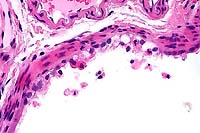

- Case 9-1 . Lung. There are abundant detached and pyknotic

epithelial cells and neutrophils within small and medium caliber

bronchioles.

- Case 9-1 . Lung. Larger bronchioles retain intact

ciliated bronchiolar epithelial cells but scattered foci have

bronchiolar epithelial cells with vacuolation, hypereosinophilia,

pyknosis, loss of cilia, and detachment (degeneration & necrosis).